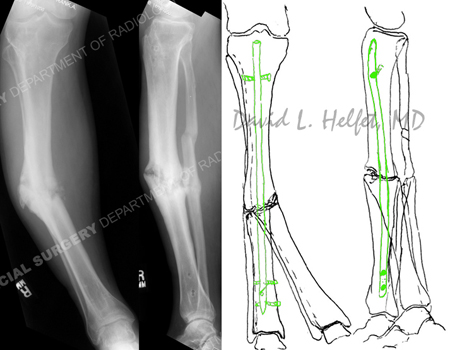

radiograph illustrating right-sided mid-shaft tibial nonunion with varus deformity from a case example for hospital for special surgery.

Radiographs (left images) illustrate a right-sided mid-shaft tibial nonunion with 30° varus deformity and 15° flexion deformity; pre-operative (right image) plan for correction of deformity and insertion of a reamed intramedullary (IM) nail.